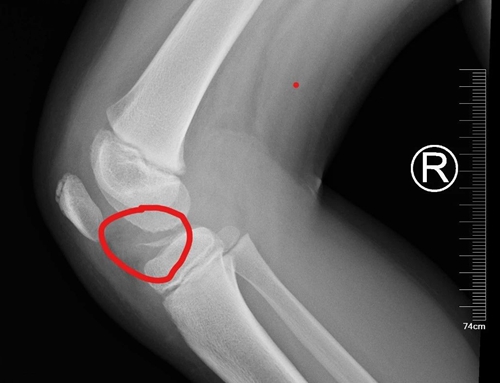

經(jīng)過檢查,接診小兒骨科專家診斷患兒脛骨髁間嵴骨折!

脛骨髁間嵴骨折好發(fā)于8-14歲的兒童,多為膝關(guān)節(jié)過伸損傷,如運(yùn)動(dòng)傷、摔傷,也可見于摩托車與自行車交通事故傷,大多數(shù)患兒負(fù)重行走困難。當(dāng)發(fā)生脛骨髁間嵴骨折,膝關(guān)節(jié)會突然腫脹、疼痛,不能伸直和行走,應(yīng)引起家長們的警惕。